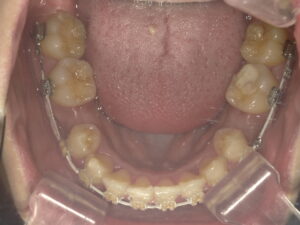

まず、下顎から矯正をスタートします。

ワイヤーが大きく歪んでいるのがわかると思います。

上下の噛み合わせを考慮し、下の歯の抜歯もしています。

ワイヤーのサイズを上げ、前歯を揃えるのと後ろに少し引いていきます。